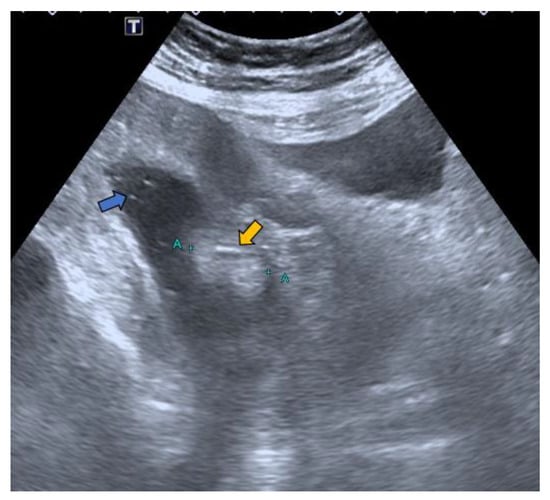

In our case, it was possible to follow up on the lipoma during biannual OCs performed because of her personal history of polyposis. Initially, it was proposed that abdominal-CT scans (Figure 1 and Figure 2) should be performed the year after each OC. This way, the size of the lesion could be monitored, and the degree of local infiltration could be determined. After the first abdominal-CT follow-up, to avoid exposure to radiation, HS (Figure 3) was included as an alternative to abdominal-CT. In the subsequent follow-up, in addition to the biannual OCs, two hydrocolonic ultrasound scans (without cleansing preparation) and one abdominal-CT scan were performed. During the seven years of follow-up, the lipoma remained stable, and the patient remains asymptomatic.

Figure 3.

Hydrocolonic sonography without cleaning preparation. The lipoma between the blue marks (A +, + A) is seen as a hyperechoic image (yellow arrow) projecting into the lumen of the cecum. Faecal remains are observed floating as hyperechoic dotted images in the lumen of the co-lon distended by the serum (blue arrow).

- Lesion size: The sensitivity of HS in the detection of lesions larger than 10 mm is 93% [20]. In our case of a lesion size of 33 mm, it was possible to avoid the discomfort associated with the cleansing preparation. In a recent study, 18 mm lesions were detected with HS without using cleansing preparation [20].

- Lesion location: The segment of the colon in which the lesion is located is an important factor if HS is to be used in follow-up. The rectum is a non-assessable segment. The position of the sigma in the pelvis, the disposition of the transverse colon [20] or the existence of dolichomegalosigma [15,20] are factors that limit the study of these colonic segments. However, the cecum, and ascending and descending colon are more superficial segments and are easier to assess by HS. Our lesion located in the cecum is accessible by HS. However, studying the cecum has peculiarities. First, the presence of faecal remains. Faecal remains frequently accumulate in the right colon [14,15,20]. Faecal remains are observed in the lumen of the colon during retrograde instillation of saline solution and can be moved by using the transducer to compress the abdomen rapidly and lightly [10,11,14,20]. Moving the patient sideways also allows the faecal matter to be displaced, allowing better visualisation. However, they can sometimes be abundant. The concentration of faecal matter can be reduced by increasing the infusion of saline solution [14] if the patient can tolerate it. It is also possible to decrease the faecal concentration by emptying and refilling the colon [20]. Thus, the saline solution together with the faecal remains return to the bag and a new bag of saline solution is used. Second, the ileocecal valve can also be mistaken for a lipoma. The ileocecal valve is seen as a pseudopolyp image projecting into the colon lumen from the ileocecal junction [38] (Figure 4). A lipoma in the cecum may be confused with lipomatosis of the ileocecal valve, which is a more common entity than lipoma [7,36].